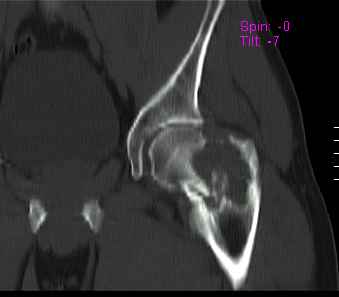

Уважаемые коллеги! Больной (1974 г.р.) травма 26.01.2009г., у пал на ра-боте с высоты своего роста, доставлен в одну из горбольниц Екатеринбурга в травматологическое отделение. На рентгенограмме выявлен патологический перелом чрезвертельной области левого бедра.

Доброкачественная опухоль (ОБК?, энхондрома?), по данным RS. Дополнительно произведено КТ. Наложено скелетное вытяжение.

Прилагаются: рентгенограмма и данные СТ

По данным рентгенограммы и СТ диагноз определить в данном случае нельзя. При дифдиагнозе можно предполагать костную кисту, остеокластому, хондрому; в нашей клинике был подобный случай - гистологически верифицирована хондромиксоидная фиброма.